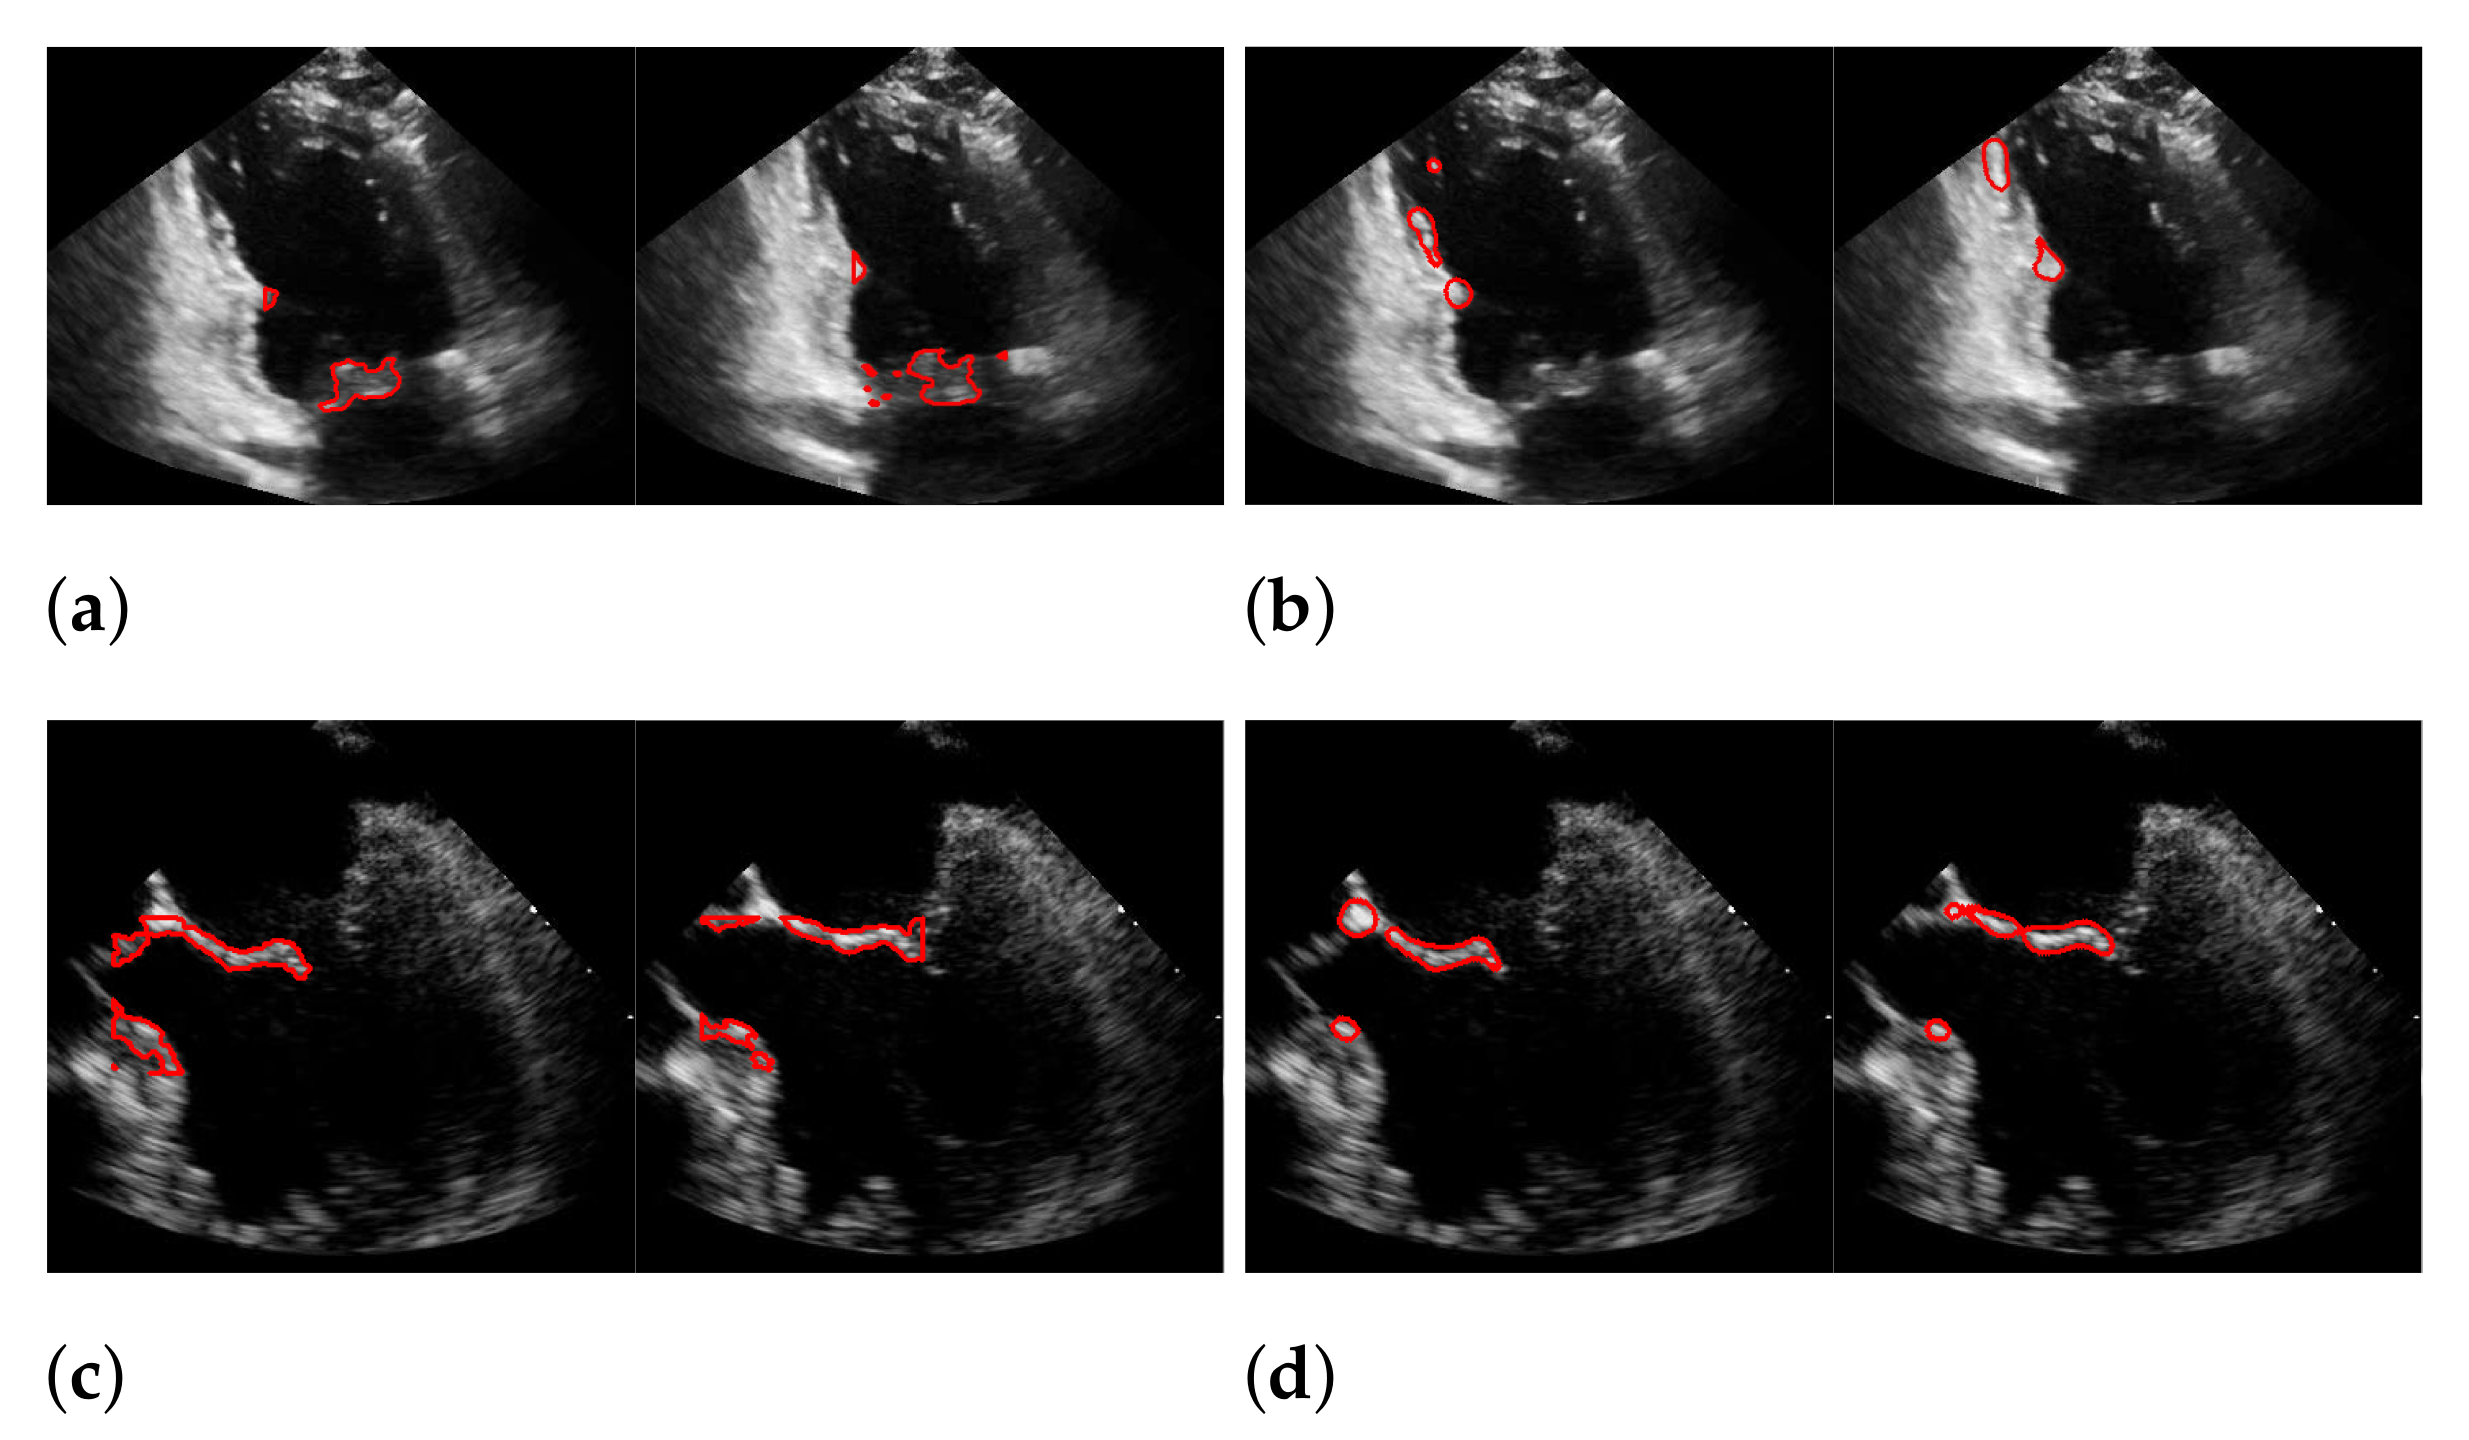

Figure 16.

Segmentation in the cases of the largest differences between the f1-scores of our approach (segmentation with windowing) (a,c) and the one of Dukler et al. (b,d). The results in (a,b) belong to the blue rightmost bar of Figure 15, the results in (c,d) belong to the leftmost bar.

In both figures (Figure 16 and Figure 18), the upper row of the segmentation by [9,40] gives an example of a missed mitral valve using a windowing technique and underlines the importance of correct valve detection. The upper row videos are especially challenging because of a partly disappearing mitral valve and weak contrast.